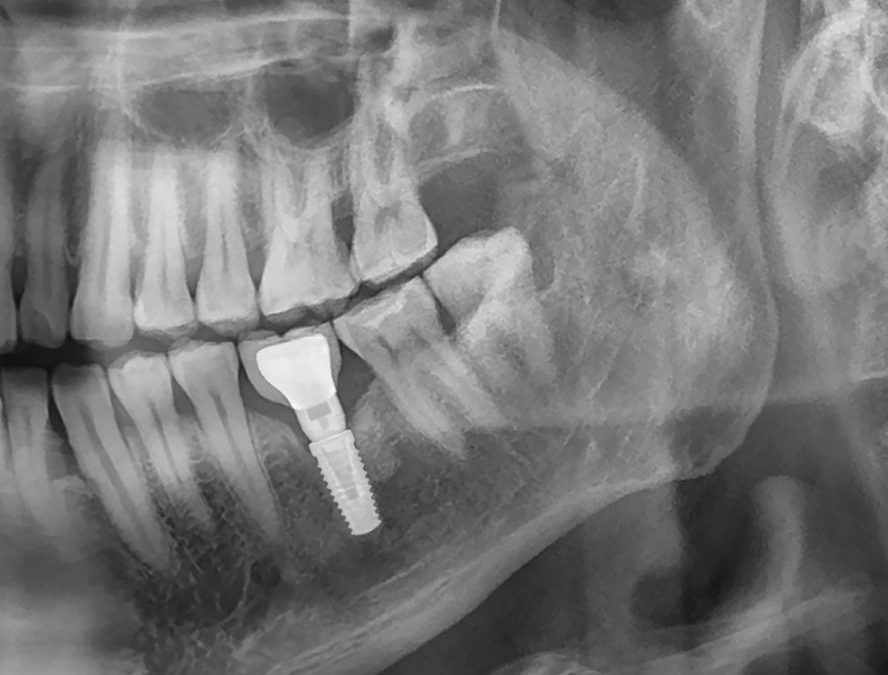

La réussite d’un implant dentaire repose sur un concept fondamental : l’ostéointégration. Il s’agit de la fusion naturelle entre l’implant et l’os de la mâchoire, garantissant à la fois la stabilité et la durabilité du traitement. À Casablanca, les cliniques spécialisées mettent un accent particulier sur la qualité de l’os et la planification chirurgicale pour assurer le succès de chaque intervention.

Un traitement par implants dentaires est une solution moderne, durable et efficace pour remplacer une ou plusieurs dents manquantes. À Casablanca, comme partout ailleurs, ce traitement se déroule selon des étapes bien définies qui visent à garantir la réussite fonctionnelle, esthétique et biologique de l’implant.

Un traitement par implants dentaires est une solution moderne, durable et efficace pour remplacer une ou plusieurs dents manquantes. À Casablanca, comme partout ailleurs, ce traitement se déroule selon des étapes bien définies qui visent à garantir la réussite fonctionnelle, esthétique et biologique de l’implant. Comprendre chaque phase du parcours permet au patient d’être mieux informé, plus serein et de participer activement à sa prise en charge.